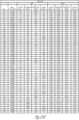

- FIGS. 25A-25H illustrate a series of tables of immunoassay plate data from a Luminex ® assay for Staphylococcus aureus (Panel A). Staphylococcus epidermidis (Panel B), Candida albicans, and Enterococcus faecalis.

- Well contents represent the controls or patient sample tested. Note that the controls for plate 1 were erroneous due to a technical error therefore the controls from plate 2 (run at the same time) were used for the assay.

- MFI median fluorescent intensity

- S.C/O signal, cut-off

- FIGS. 26A-26R illustrate a table of individual sample cell and culture data of FIGS. 25A-25H , listed in sample order, S/CO and MID immunoassay interpretation, ⁇ -defensin >1 is positive, C-reactive protein (CRP) >3 is positive, total nucleated cells (TNC >3000 is positive).

- Organism organism identified through culture at a maximum of 7 days; most samples (>95%) culture positive within 2 days